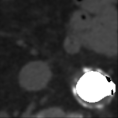

| Patient | Basal | CM | Processed | Superposed | |

|---|---|---|---|---|---|

| P14 | -0.013 | ||||

| P19 | -0.003 | ||||

| P20 | -0.569 | ||||

| P22 | -0.191 | ||||

| P26 | -0.235 | ||||

| P30 | -0.222 |